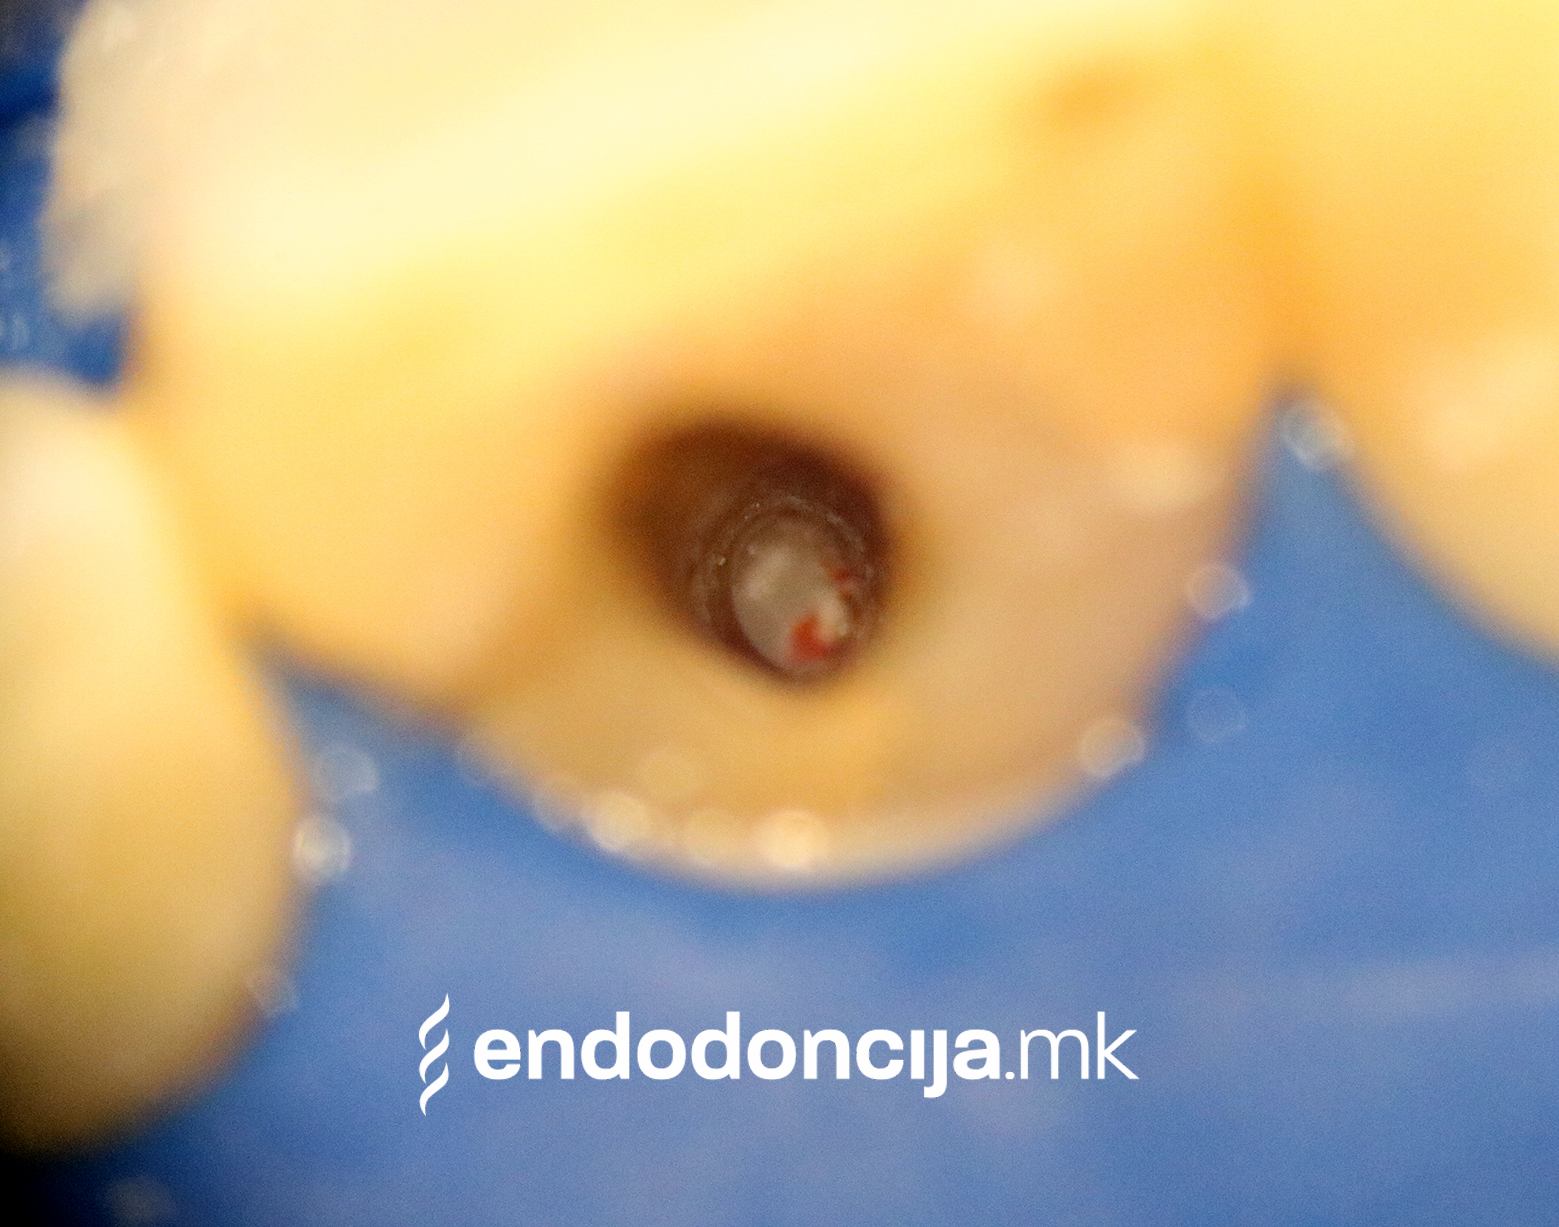

На специјализираниот оддел за ендодонција, нашите пациенти ги лекуваме на највисоко професионално и дијагностичко ниво. Опремени сме со најсовремени хируршки микроскопи, кои поддржуваат детален приказ и подготовка на коренот и нудат комплетно ново ниво на прецизност. Најновата ендодонтска опрема, инструментите и материјалите за полнење се во секојдневна употреба. На овој начин третманот станува пократок, дури и во комплицирани случаи, и се избегнува губење на забите.

Она што е импресивно е прецизноста на микроскопските третмани. Дури и кога каналите се потешко достапни, може да се лоцираат и исчистат така што релапсите се со помала веројатност. Спротивно на тоа, скриените канали често остануваат неоткриени во конвенционалниот третман на коренскиот канал и затоа не можат да се чистат. Бактериите можат да се размножуваат таму без пречки и да предизвикаат воспаленија. Ова често останува незабележано со години додека не се појави забоболка, а со тоа и компликации.

Употребата на микроскоп исто така овозможува детектирање пукнатини или фрактури што може да предизвикаат болка или воспаление.